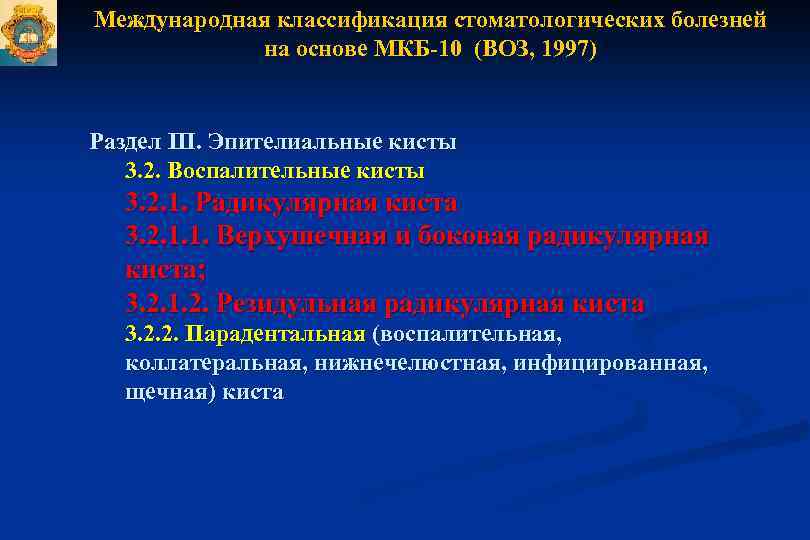

Код мкб 10 атерома головы

Код мкб 10 атерома головы 109 фото